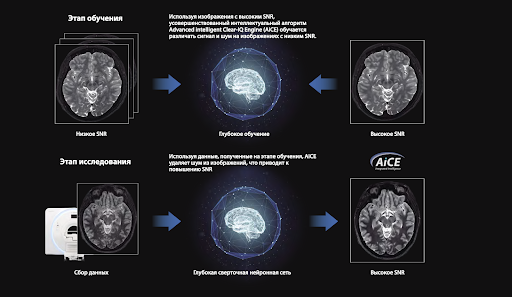

Качество диагностики

Технология Advanced intelligent Clear-IQ Engine позволяет получать МР-изображения с безупречной детализацией структур. Нейронная сеть реконструирует данные с низким отношением «сигнал/шум», улучшая SNR изображений.

Advanced intelligent Clear-IQ Engine (AiCE)